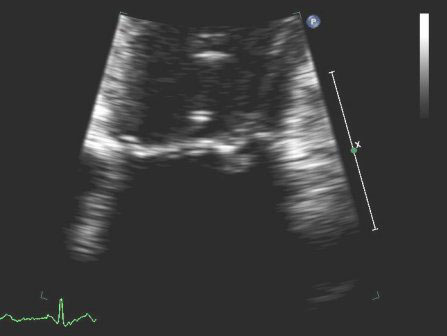

Regurgitação mitral

Prolapso posterior da valva mitral no ecocardiograma em modo M

Do acervo de Samir Kapadia e Mehdi H. Shishehbor